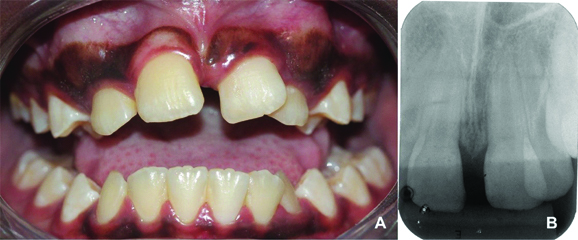

Extraoral clinical examination revealed the presence of oedema in the region between the nose wing and upper lip on the right side of the face, causing slight facial asymmetry [Table/Fig-1a]. The intra-oral examination revealed that the patient had mixed dentition and was caries free [Table/Fig-1b]. He had unsatisfactory oral hygiene, with biofilm on all teeth. A normal overbite and overjet, presence of midline deviation, eruption of tooth 21 in gyroversion, crossbite of teeth 21 and 22 and crowding were verified. The presence of a painless increased volume of hard consistency in the region of the upper central right incisor and the prolonged retention of the primary upper central incisors were observed [Table/Fig-1c].

a) Extraoral view showing slight facial oedema on the right side of the face and asymmetry. b) Intraoral occlusal upper photography showing the prolonged retention of the primary upper central incisors and the tooth 21 in gyroversion. c) Frontal view showing midline deviation and crossbite of teeth 21 and 22.

One week after surgery, patient visited for suture removal and evaluation of the local tissue healing, which was satisfactory. Further clinical and radiographic follow-up evaluations were carried out every six months, and there was spontaneous eruption of the permanent upper central right incisor. The patient was happy and has shown to be more confident and more smiling during consultations. The parents were instructed to seek orthodontic treatment at the end of the exfoliation of the primary teeth. Meanwhile, he continued to receive preventive health care and clinical and radiographic evaluations, that completed 18 months of follow-up [Table/Fig-5].

a) Intraoral frontal view and b) periapical radiography after 18 months of follow-up.